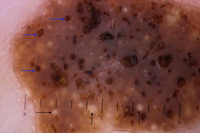

Example of a dark-brown pigmented seborrheic keratosis. Dermoscopic image: see yellowish horn pearls and dark brown holes corresponding to so-called "pseudo-follicular openings"

From the collection of Dr Braun and Dr Kolm, used with permission